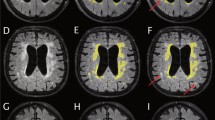

In childhood hydrocephalus, both the amount of cerebrospinal fluid and the brain volume are relevant for the prognosis of the development and for therapy monitoring. Since classical planar measurements of ventricular size are subject to strong limitations, imprecise and neglect brain volume, 3D volumetry is most desirable. We used and evaluated the robust segmentation algorithms of the freely available FSL-toolbox in paediatric hydrocephalus patients before and after specific therapy.

Retrospectively 76 pre- and postoperative high-resolution T2-weighted MRI sequences (true FISP, 1 mm isovoxel) were analyzed in 38 patients with paediatric hydrocephalus (mean 4.4 ± 5.1 years) who underwent surgical treatment (ventriculo-peritoneal (VP) shunt n = 22, endoscopic third ventriculostomy (ETV) n = 16). After preprocessing, the 3D-datasets were skull stripped to estimate the inner skull surface. Following, a 2 class segmentation into different tissue types (brain matter and CSF) was performed. The volumes of CSF and brain were calculated.

The method could be implemented in an automated fashion in all 76 MRIs. In the VP shunt cohort, the amount of CSF (p < 0.001) decreased. Consecutively brain volume increased significantly (p < 0.001). Following ETV, CSF volume (p = 0.019) decreased significantly (p = 0.012) although the reduction was less pronounced than after shunt implantation. Brain volume expanded (p = 0.02).

A reliable automated segmentation of CSF and brain could be performed with the implemented algorithm. The method was able to track changes after therapy and detected significant differences in CSF and brain volumes after shunting and after ETV.